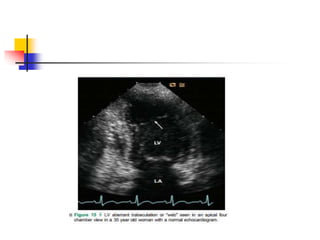

 false tendons are fibromuscular structures crossing

the LV cavity.

 LV bands may pass between papillary muscles, from

papillary muscle to the ventricular septum, between

free walls, or from free wall to interventricular septum,

in contrary to true chordae tendineae connecting

papillary muscle and mitral valve leaflets.

 False tendon is found up to 55% in normal hearts by

autopsy .

 In echo, LV bands appear as string-like thin bands

passing LV cavity , which may be transverse,

longitudinal, or sagittal, and single or multiple.

 location, direction, length and thickness of LV bands

may vary depending on their embryonic origin of

inner cardiac muscle layer and contents.

 Muscular bands become shorter and thicker in

systole, and vice versa in diastole.

 Fibrous bands become straight and taut in diastole,

and vice versa in systole.

 Off-axis images demonstrating the overall length of

bands, normal LV structures on both ends, and

constant motion during cardiac cycle are the key

features.

 False tendon located near LV apex may be confused

for mural thrombus particularly in images of true LV

apex being not completely visualized.

 False tendonis found up to 55% in normal hearts by autopsy .  In echo, LV bands appear as string-like thin bands passing LV cavity , which may be transverse, longitudinal, or sagittal, and single or multiple.  location, direction, length and thickness of LV bands may vary depending on their embryonic origin of inner cardiac muscle layer and contents.

 Muscular bandsbecome shorter and thicker in systole, and vice versa in diastole.  Fibrous bands become straight and taut in diastole, and vice versa in systole.  Off-axis images demonstrating the overall length of bands, normal LV structures on both ends, and constant motion during cardiac cycle are the key features.  False tendon located near LV apex may be confused for mural thrombus particularly in images of true LV apex being not completely visualized.